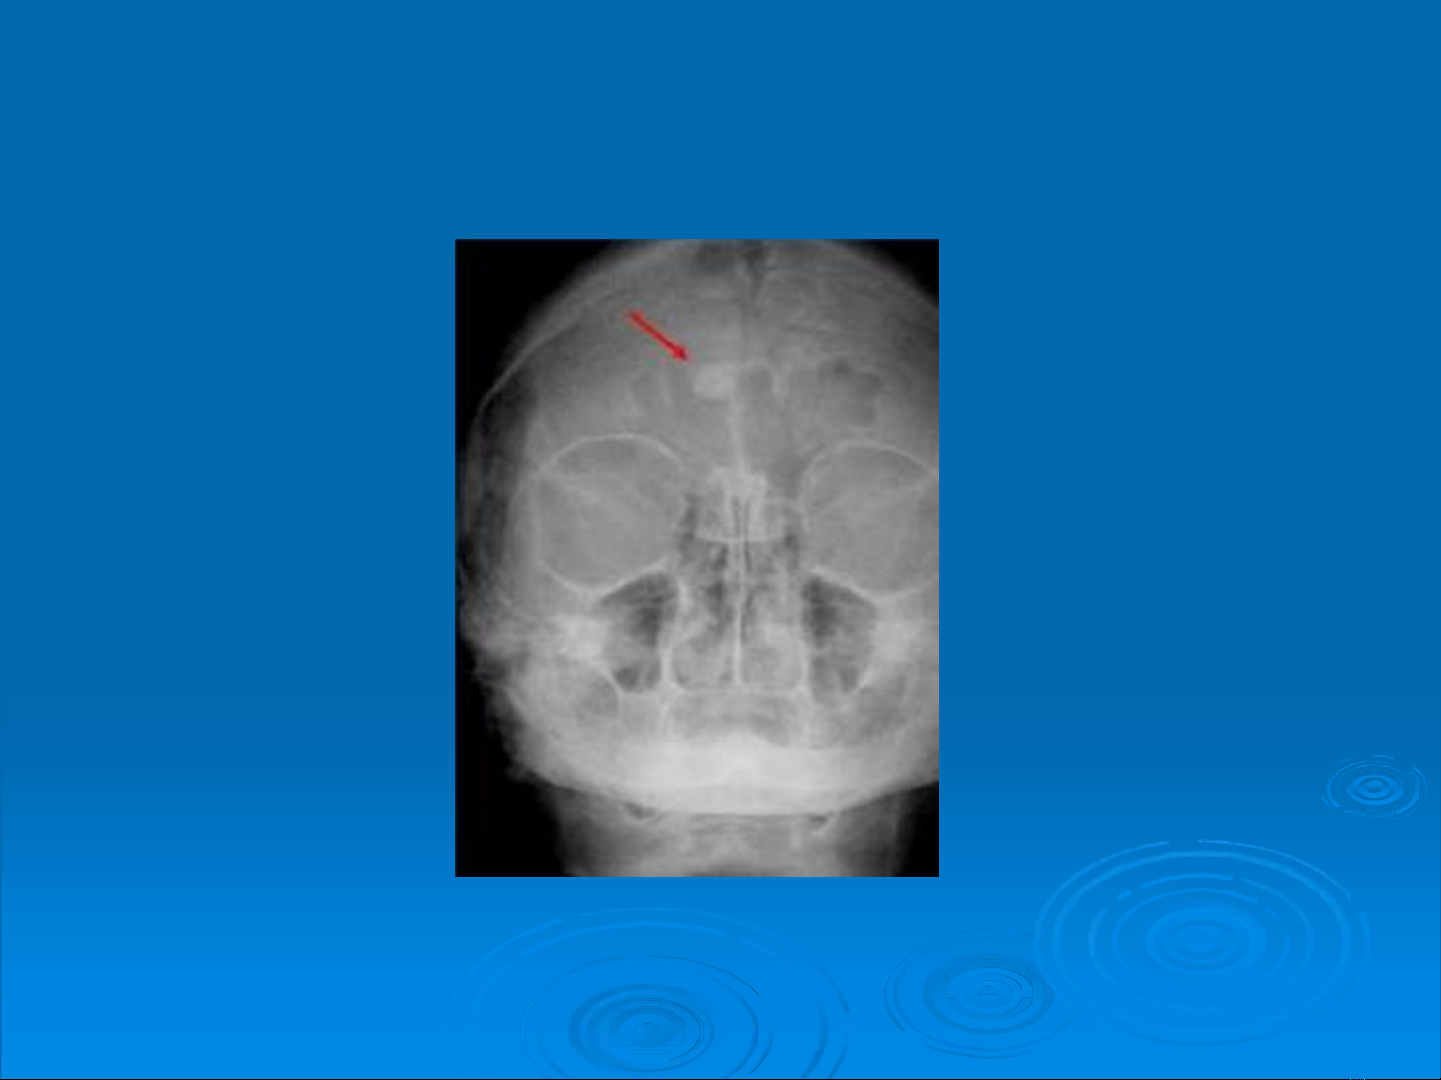

a.U xương lành tính (osteoma)

- Vị trí hay gặp: Xương sọ, xoang mặt và các chi.

- Hình ảnh :

+ U thường đơn độc.

+ Hình mờ đậm đồng đều, các xương mọc thêm

cũng thấy rõ thớ xương.

+ Hình tròn hoặc bầu dục, bờ viền liên tục rõ nét.

+ Không bao giờ có hình ảnh viêm màng xương.

OSTEOMA XƯƠNG SỌ